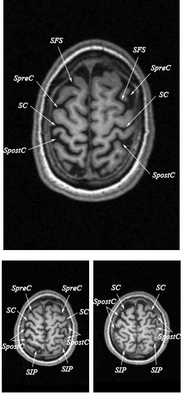

Знание анатомии мозга очень важно для правильной локализации патологических процессов. Ещё более важно оно для изучения самого мозга с помощью современных «функциональных» методов, таких как функциональная магнитно-резонансная томография (fMRI), и позитронно-эмиссионная томография. С анатомией мозга мы знакомимся ещё со студенческой скамьи и существует множество анатомических атласов, в том числе и поперечных сечений. Казалось бы, зачем ещё один? На самом деле, сравнение МРТ срезов с анатомическими приводит к множеству ошибок. Это связано как со специфическими особенностями получения МРТ изображений, так и с тем, что строение мозга очень индивидуально.

Представленная страница сайта основана на специальном изучении МРТ головного мозга здоровых лиц. Для этого изображения получали с минимальной величиной воксела (1 мм в каждом измерении), что исключало наслоения борозд. Каждая из структур прослеживалась в трёх реконструированных плоскостях путём её выделения с помощью компьютерной программы. Мы рассматривали различные анатомические варианты, что обсуждается в работе. В результате, учитывая вариабельность строения мозга, подобран условно «стандартный» мозг. Поскольку на сайте нереально представить 128 срезов в каждой из основных плоскостей, мы ограничились только каждым пятым срезом. Основные срезы в поперечной плоскости даны без наклона назад (угол 0º). Под ними для представления о изменении соотношения анатомических структур демонстрируются срезы, выполненные на тех же уровнях, но с наклонами назад -15º и -30º.

Список сокращений

Борозды

Междолевые и срединные

SC - центральная борозда

FS - Сильвиева щель (латеральная борозда)

SpreC - предцентральная борозда

SFS - верхняя лобная борозда

SpostC - постцентральная борозда

SIP - внутритеменная борозда